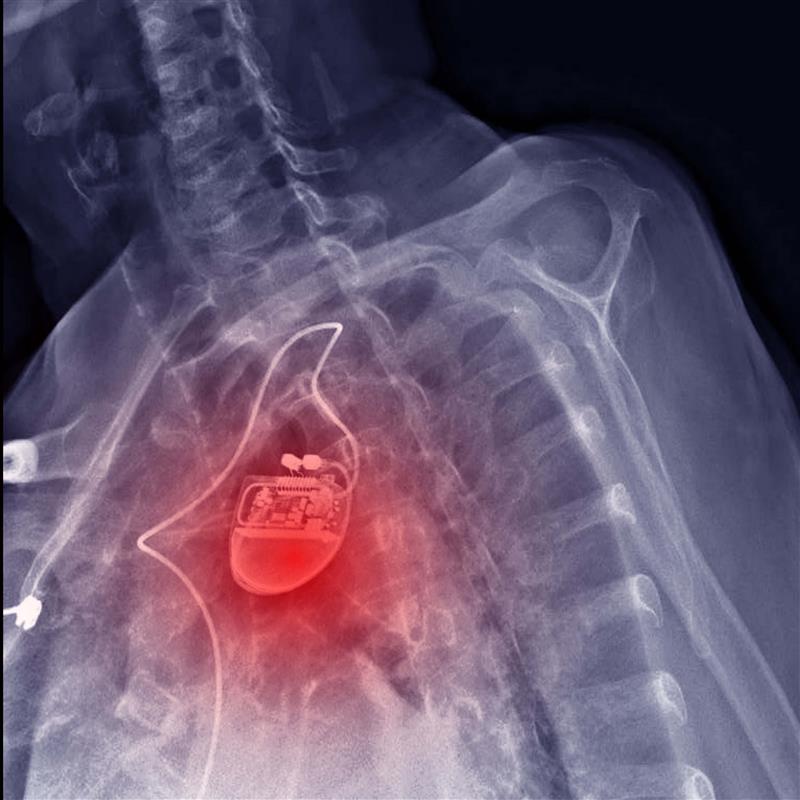

العلاج بإعادة تزامن القلب

يُستخدَم العلاج بإعادة تزامن القلب (Cardiac resynchronization therapy, CRT) في المرضى الذين يعانون من قصور القلب والاضطراب في نظام التوصيل الكهربائي القلبي، وذلك من خلال زرع جهاز صغير تحت الجلد في منطقة الصدر، يُسمّى مُنظِّم ضربات القلب ثنائي البطين (Biventricular Pacemaker)[21]. يقوم مبدأ عمل هذا الجهاز على إرسال إشارات كهربائية بسيطة تُحفِّز كلا البُطينَيْن الأيمن والأيسر على الانقباض في الوقت ذاته، ما يؤدي إلى تحسين الانقباض القلبي وزيادة النتاج القلبي، وتخفيف الأعراض مثل ضيق التنفّس والتعب. ولكن، توجد بعض المخاطر التي يجب أن تُوضَع في الحسبان، مثل تغيُّر موقع الجهاز، والنزيف أو التورم، وإخفاق الجهاز[22] (الشكل 2).​